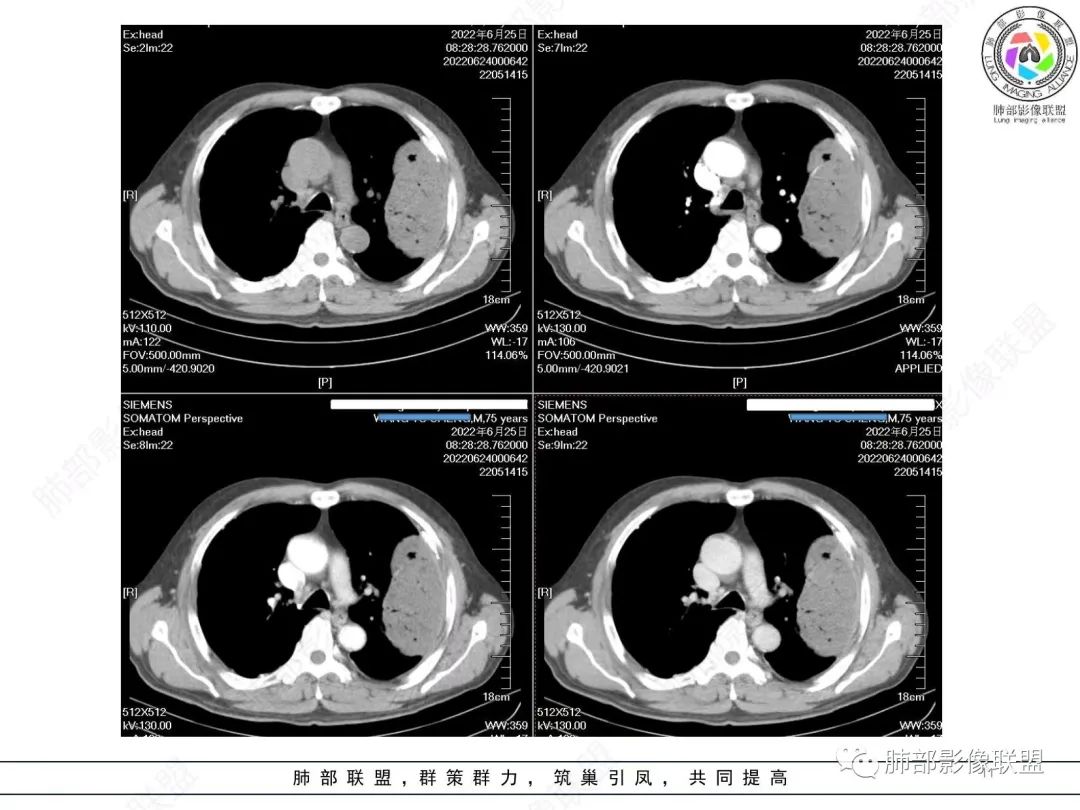

左肺上叶大肿块,膨胀性生长,边界清,密度较低,见部分坏死区,强化弱,肿块见支气管充气V扩张征,分布僵直,枯树枝特点,另一个重要特点血管造影征,淋巴瘤,肿块长轴与胸膜平行,与隐球菌鉴别,隐球荚膜抗原检查,明确诊断经皮肺穿刺。另胸膜钙化(问诊既往有无患胸膜炎病史)。

老年男性,糖尿病病史,消瘦、乏力三个月,影像表现左肺上叶胸膜下团块,有一定张力,内部疏松,可见支气管影及坏死区,增强病灶边缘环形强化,内部未见强化,考虑炎性肉芽肿病变,隐球?奴卡?放线菌?鉴别淋巴瘤。

左肺上叶胸膜下肿块,宽基底与胸膜相连,跨叶裂,边缘清晰膨隆,其内支气管充气,部分扩张、僵直,无明显强化,血管造影征,考虑淋巴瘤,鉴别腺癌

左肺胸膜下巨大占位,跨叶裂,宽基底与胸膜相连,胸膜钙化,平扫密度较低,强化不明显,可见内部血管显影,支气管充气征和扩张,考虑为恶性,倾向于淋巴瘤

增强没有强化,血管束正常,气管束有正常有扩张,内有空洞,考虑炎性病变,隐球?

左侧胸腔巨大肿块,跨叶生长,临近胸膜钙化,边缘模糊,可见支气管影,定位肺内,增强后轻度强化,边缘见血管影,考虑淋巴瘤,鉴别肉瘤

老年,明显消瘦,左侧胸廓轻度缩小?胸膜增厚,见钙化,以前结核?接触其他?整个肿块膨隆,坏死不明显,支气管通畅,轻度扩张轻度强化,考虑恶性,淋巴瘤可能

左肺上叶胸膜下肿块,膨胀性生长,边界清晰,密度不均部分坏死,未见强化,病灶内支气管迂曲扩张,病灶长轴与胸膜平行,胸膜下脂肪间隙存在,胸膜钙化,考虑放线菌?毛霉?鉴别淋巴瘤

支持淋巴瘤,左上肺大肿块,有分叶,边缘光整,病灶内密度不均,可见支气管扩张征,增强后可见血管影征。周围肺野清晰。

左肺上叶肿块,宽基底与胸膜相连,跨叶裂,边缘清晰膨隆,可见小分叶,其内支气管充气,部分扩张、僵直,呈枯枝征,支气管达边征,增强无明显强化,可见血管造影征,考虑恶性病变,淋巴瘤,鉴别粘液腺癌。

左肺团块样病灶,分叶,膨隆,不规则空洞,支气管枯枝样,血管造影征,考虑恶性,腺癌(肺肠型)。